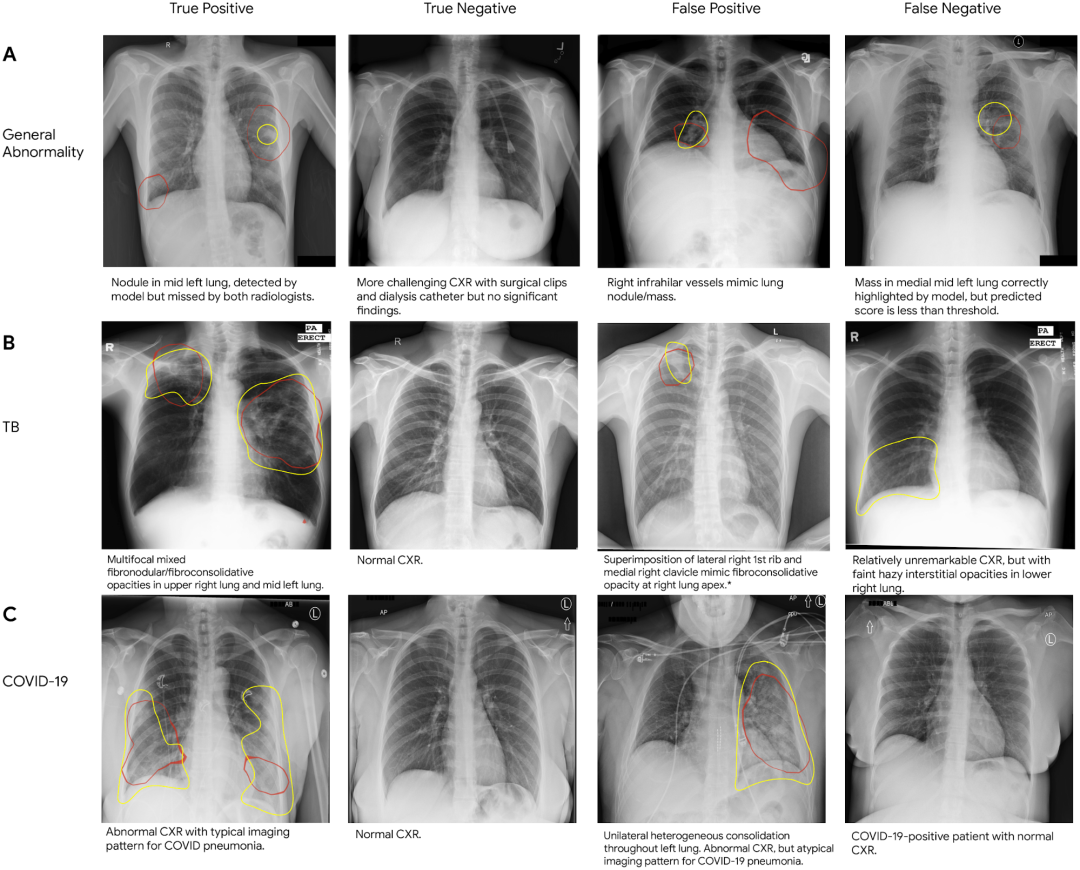

胸部 X 光片的真假阳性及真假阴性样本,(A) 代表一般异常情况,(B) 代表结核病,(C) 代表新冠肺炎。在每张 CXR 上,我们用红色勾勒出模型重点识别为异常的区域(即类激活图),并用黄色勾勒出放射科医生指出的兴趣区域

• 类激活图

https://arxiv.google.cn/abs/1610.02391